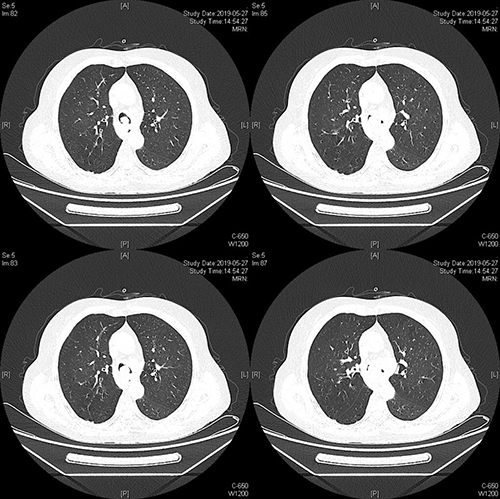

5月27日下午14:00,一名大气道95%狭窄的高危病人,搭乘外地120急救车慕名来到我院呼吸与危重症医学科姜淑娟专家门诊就诊,经初诊后,由于情况紧急,立即通过绿色通道办理入院,并同时安排复查胸部CT了解病情。

经进一步检查发现,该患者大气道狭窄95%,病人随时可能因为痰液窒息而亡!